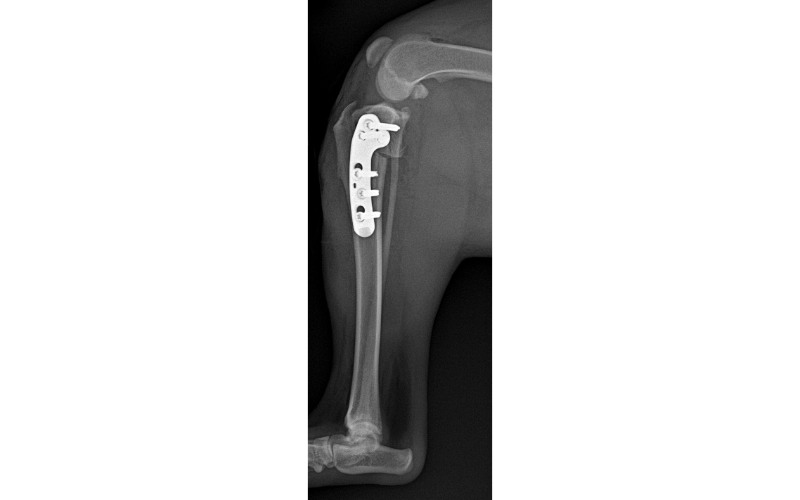

Next, a semicircular cut is made into the top portion of the tibia and the segment is rotated backward to create a flatter tibial slope. The two pieces of bone are then held in place with a stainless steel bone plate that is screwed onto the bone. See the X-rays pre and post-TPLO surgery (fig 2 [Pre-op. Steep slope.] & fig 3 [Post-op. Flatter slope]).

Follow-up – All TPLO patients are recommended to have an 8-10 week post-op X-ray to assess bone healing. Recommendations for returning to normal activity will be given after assessment of the X-rays.